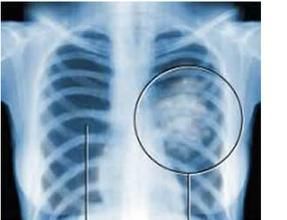

異常結果: (1) 咳嗽,多為刺激性咳嗽。 (2) 痰中帶血,多為血絲痰。 (3) 胸悶胸痛,一般症狀輕,定位模糊。當癌瘤侵及胸膜、胸壁時,疼痛加劇,定位較前明確、恆定。 (4) 氣促,癌瘤阻塞所致的肺炎、肺不張、惡性胸腔積液、瀰漫性肺泡病變等均可引起。 (5) 發熱,阻塞性肺炎或癌性毒素所致。 (6) 晚期患者可出現較明顯的惡病質。 需要檢查的人群:有上述刺激性咳嗽,痰中帶血,瀰漫性肺泡、阻塞性肺炎等肺部疾病症狀的患者。

肺澱粉樣變性,老年人肺結核,肺地絲菌病,百草枯中毒,肺結核,胸腔積液,肺放線菌病,肺動靜脈瘤,惡性葡萄胎,肺動脈口狹窄、肺炎等。